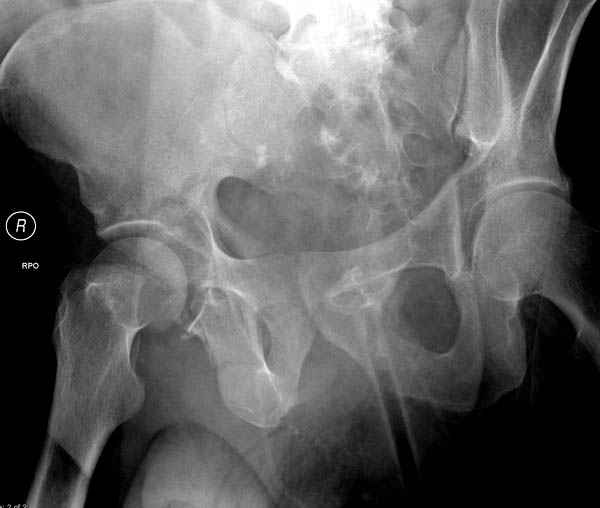

Дополнительно имеется перелом ацетабулума: задняя

колонна с полупоперечным переломом, и переломы костей лица.

Извиняюсь за качества снимков, обычный больной в 300 фунтов, портативным ренген аппаратом не пробить.

Очень хорошаая работа, поздравляю! Хотелось бы увидеть снимок таза до операции. Каким образом и как долго предполагаете разгружать тазобедреннй сустав в дальнейшшем?

По возможности вышлите снимки, сканы таза до реконструкции, интраоперационные.

По снимку создается впечатление о высоком поперечном переломе, задней колонны, стенки; почему не пользовались *magic screw*?